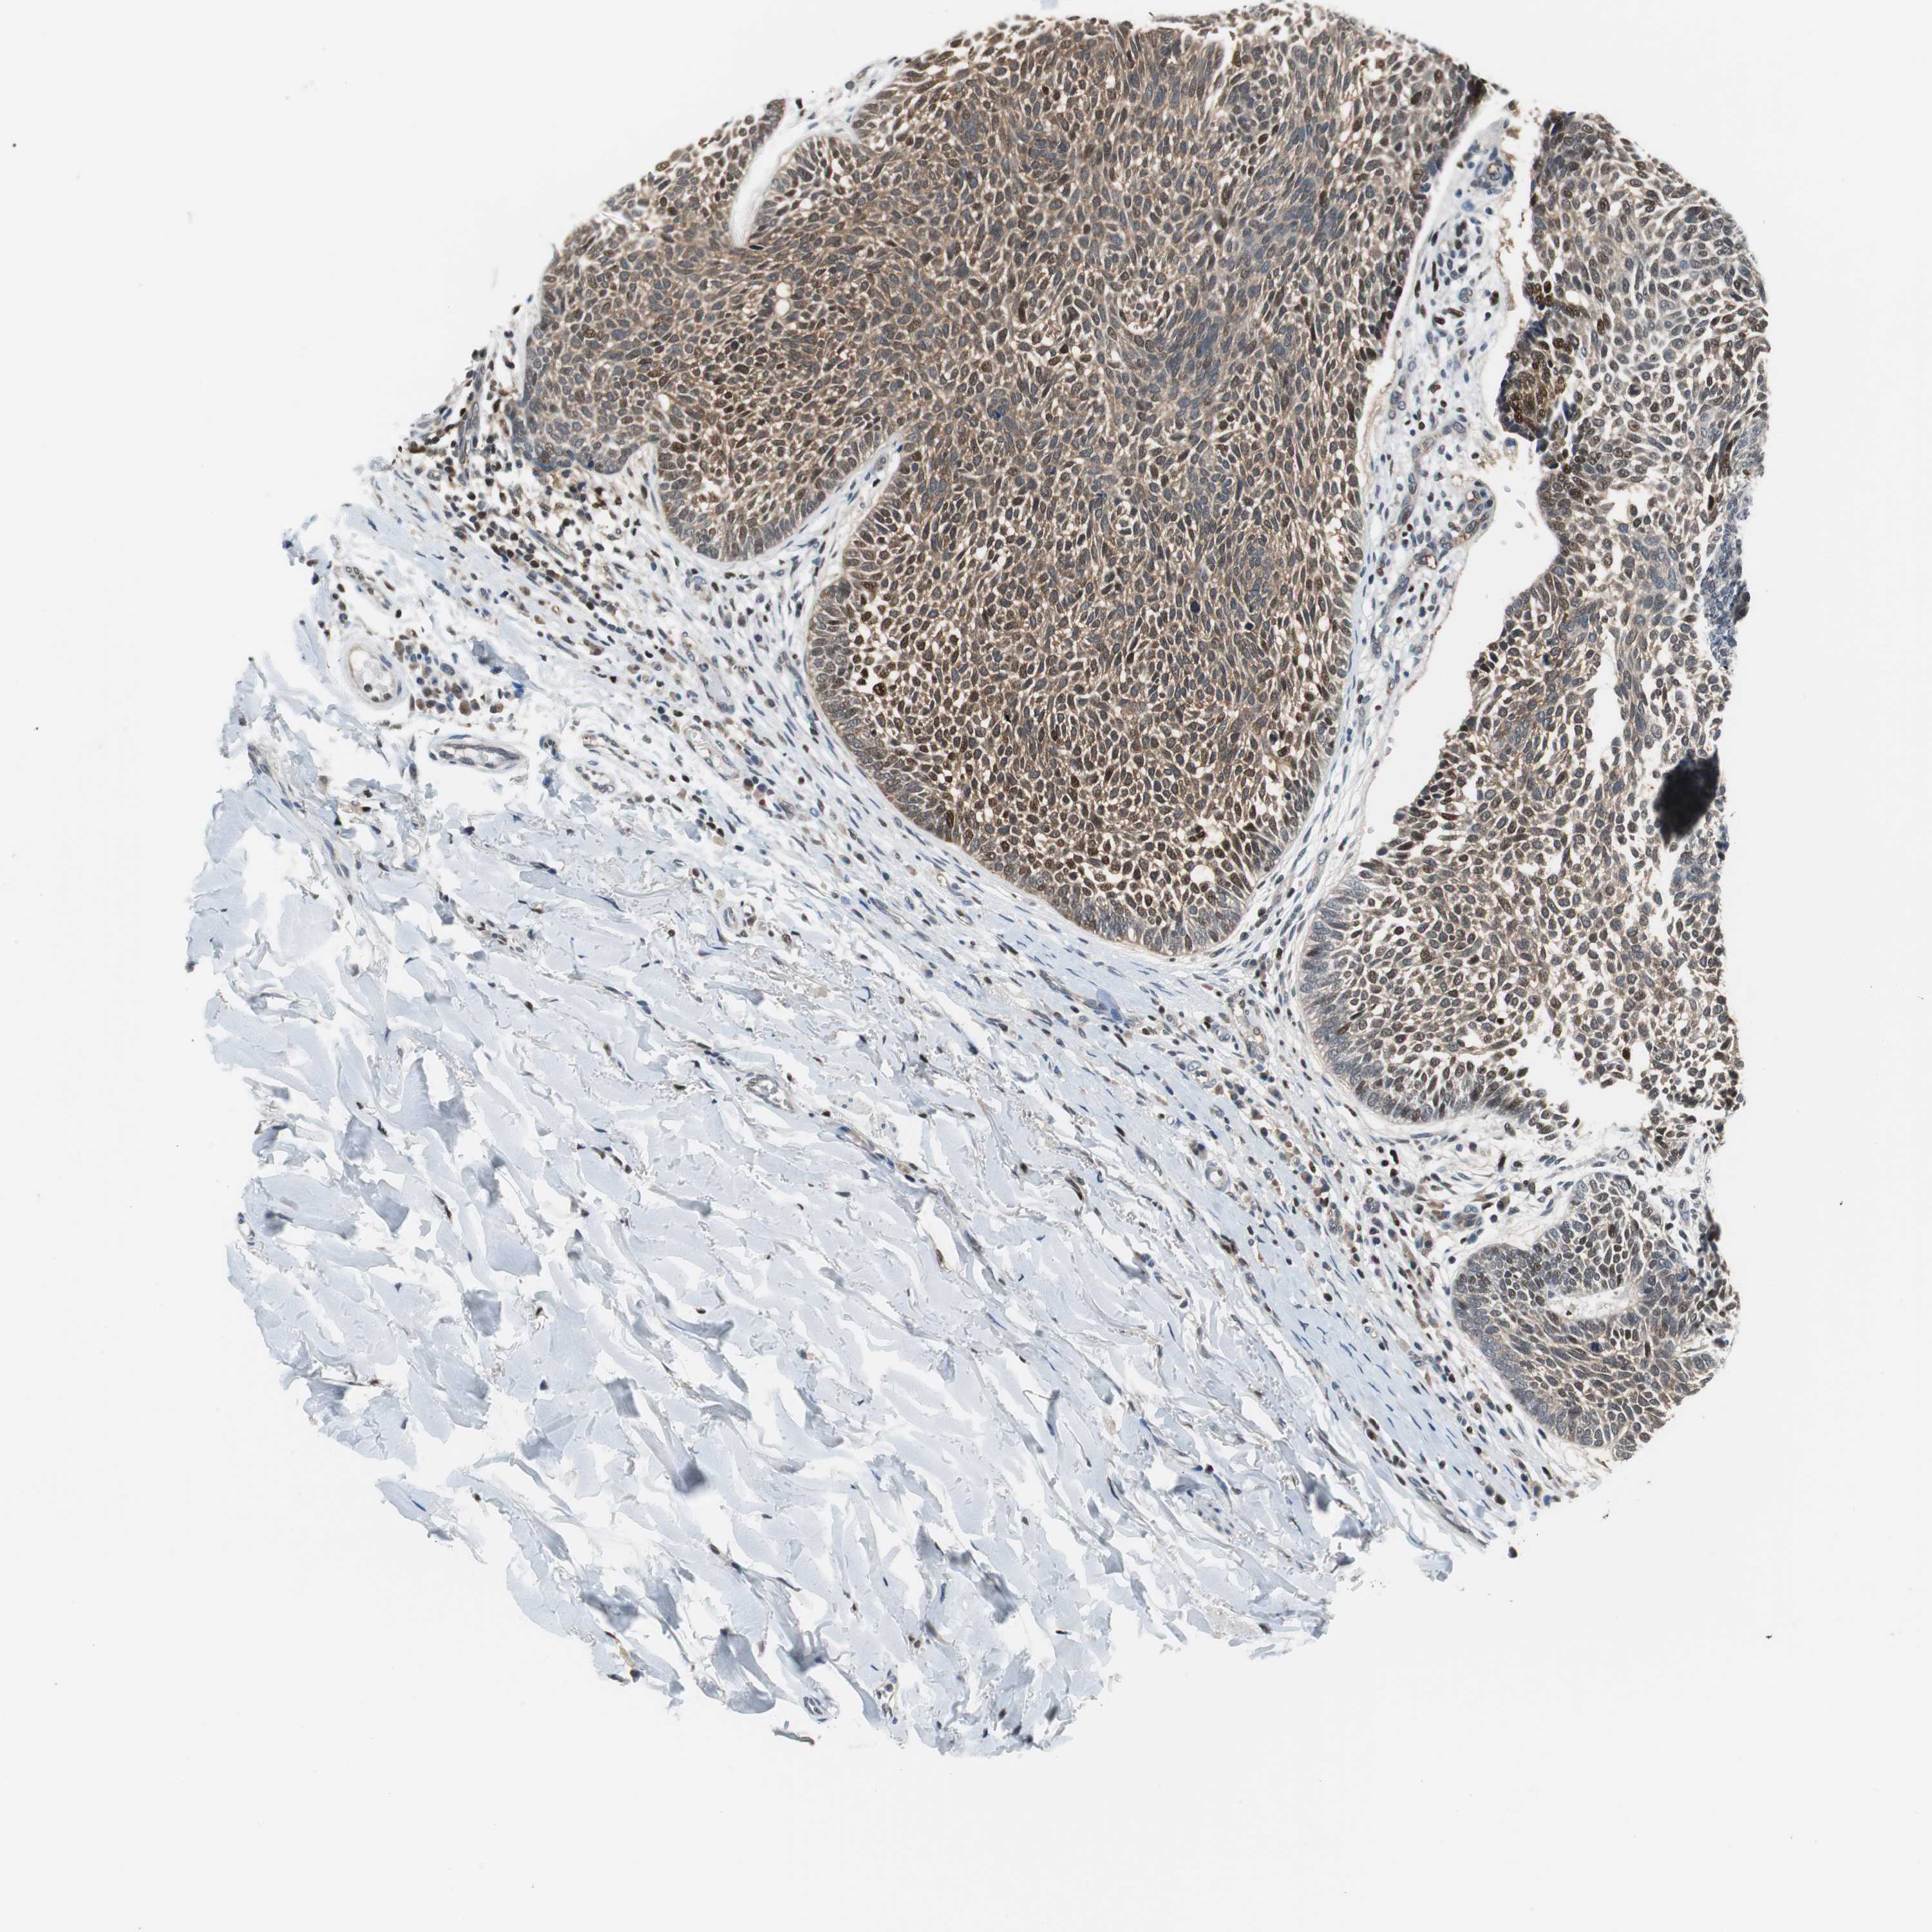

SKIN CANCER - Protein expressioni

A mouse-over function shows sample information and annotation data. Click on an image to view it in a full screen mode. Samples can be filtered based on level of antibody staining by selecting one or several of the following categories: high, medium, low and not detected. The assay and annotation is described here.

Antibody stainingi

Antibody staining in the annotated cell types in the current human tissue is reported as not detected, low, medium, or high, based on conventional immunohistochemistry profiling in selected tissues. This score is based on the combination of the staining intensity and fraction of stained cells.

Each image is clickable and will lead to virtual microscopy that enables deeper exploration of all samples and also displays staining intensity scores, fraction scores and subcellular localization as well as patient and tissue information for each sample.

Antibody HPA005653

Staining

High

Medium

Low

Not detected

Intensity

Strong

Moderate

Weak

Negative

Quantity

>75%

75%-25%

<25%

None

Location

Nuclear

Cytoplasmic/membranous

Cytoplasmic/membranous,nuclear

Squamous cell carcinoma, NOS

Basal cell carcinoma